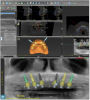

Next, a 3-dimensional (3-D) cone beam computed tomography (CBCT) scan was performed  with the immediate dentures (with radiographic markers attached) using the dual scan protocol (Figure 1).17The occlusal, cameo, and intaglio surfaces of the existing dentures were also scanned using an intraoral scanner. An online collaborative implant planning meeting between the implant surgeon and the restorative dentist permitted the formulation of a virtual prosthetic-driven treatment plan. Various treatment options were presented to the patient, such as implant-supported overdentures (utilizing four and six implants), and implant-supported fixed prostheses (metal-acrylic, zirconia, porcelain fused to metal). The patient had limited finances; however, he desired fixed implant-supported prostheses for the maxillary and the mandibular arches. It was planned that, of the options discussed earlier, the LOCATOR FIXED attachment system would be used.

Six implants were planned for both the maxillary and the mandibular arches, respectively (Figure 2 and Figure 3). A dual-arch CBCT was taken (Dentri-Max, HDX WILL; alternatively: CS 9600, Carestream; Explorer PRO, PreXion). The CBCT planning data was sent to the manufacturers to fabricate computer-

aided aided design/computer-aided manufacturing (CAD/CAM) maxillary and mandibular surgical guides for guiding with the implant placement.18,19An online virtual planning meeting was set up through Absolute Dental Navigation team. Using treatment planning software (coDiagnostiX software; alternatively: RealGuide  Universal Open system; SMOP, Swissmed), of two alternative products] the authors finalized the treatment plan, including diagnostic digital wax-up, surgical guides, and provisionals. It was decided that the existing maxillary immediate denture should continue to be used during the healing phase; however, an immediate fixed implant-supported restoration was planned for the mandibular arch.

Fig 2. Implant planning for the maxillary arch for the patient of Case Study 1.

Figure 2